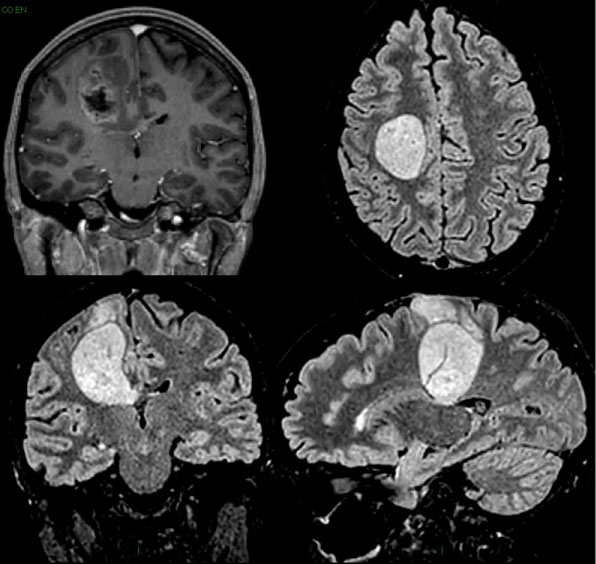

A 33-year-old woman in the 34th week of pregnancy presented with a mild left leg weakness. She was admitted to the Neurological division of our hospital. MRI scan of the brain showed a right rolandic lesion that extended to the middle third of corpus callosum and thalamic region, with a contrast-enhancing nodule, without spectroscopic evidence of necrosis (Figure 1). Two days after, the patient suddenly presented with a complete left hemiplegia. A second urgent MRI showed a dramatic increase in tumor volume due to intralesional hemorrhage (Figure 2). INR, PTT and platelet count were in normal ranges and the patient did not use antiplatelet drugs.

Figure 2: Second MRI, performed two days later, showing the hemorrhagic infarction of the previously diagnosed glioma. View Figure 2